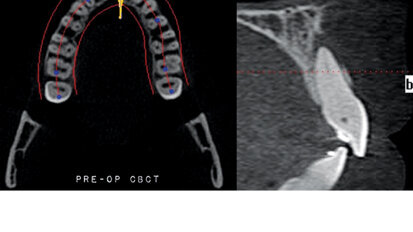

Nový úsměv za jeden den

Čt. 28. května 2020